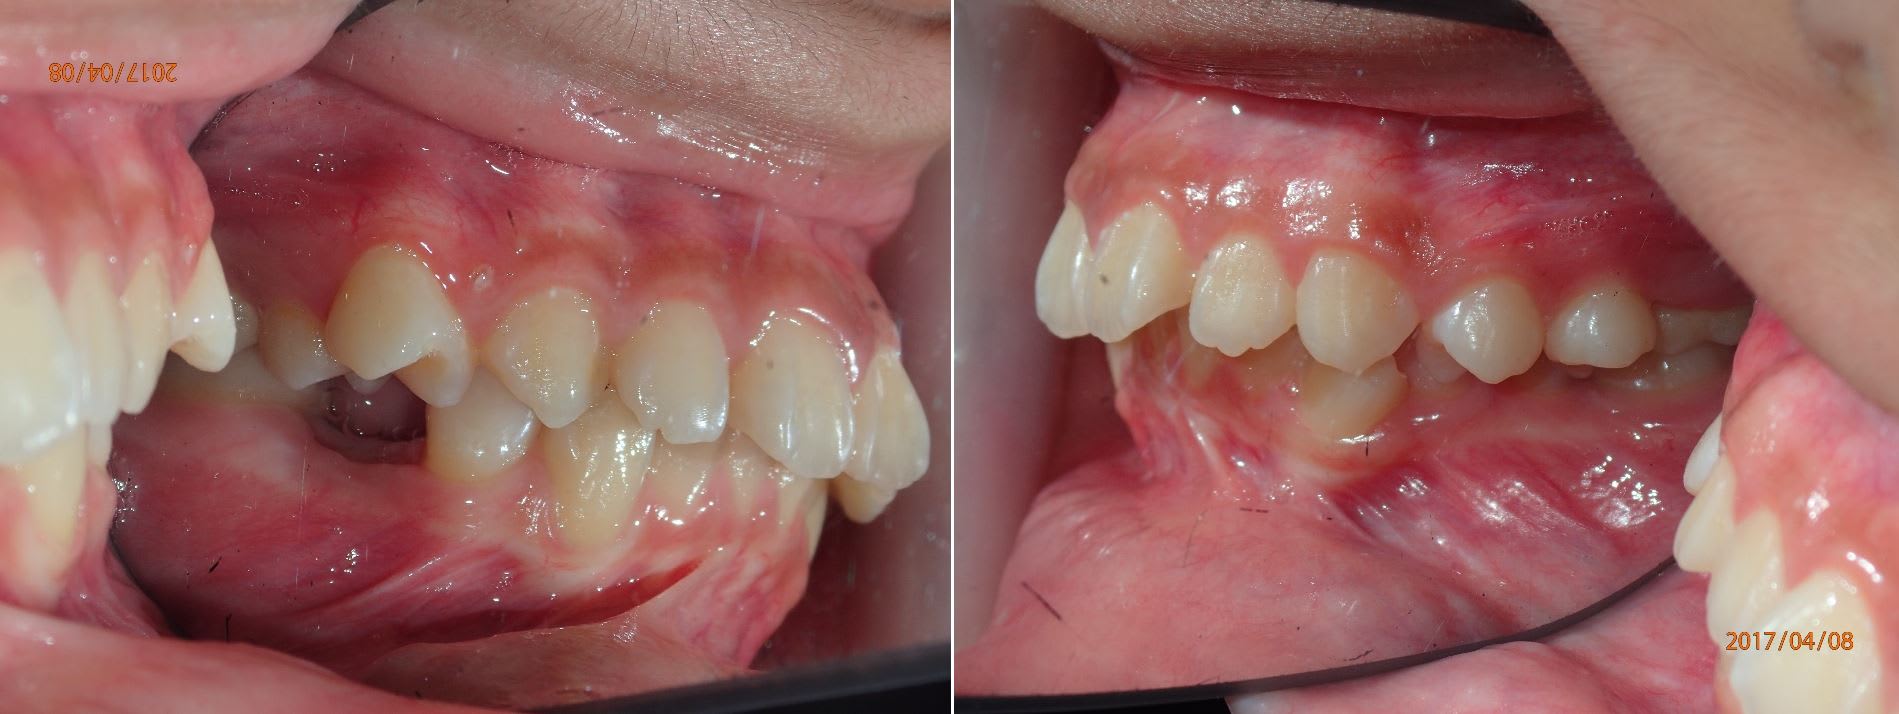

Et mon plus beau cross bite ça reste toujours celui ci.

Cross bite de plus de 7 mm plus les 7 a redresser et les espace de 6 à fermer.

C'est le cross bite crocodile Dundee.

Mais c'est pas un cross bite ça, ça c'est un cross bite.

Bravo seespan ,

la rétrognathie mandibulaire est très bien corrigée

et la ligne esthétique est parfaite

le profil du patient n'est plus convexe .

la chirurgie n’était pas necessaire !